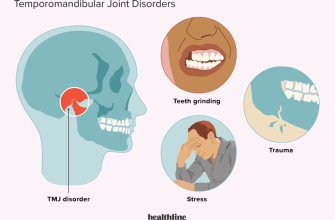

Jaw clenching, also known as teeth grinding or bruxism

Jaw pain, also known as temporomandibular joint (TMJ)